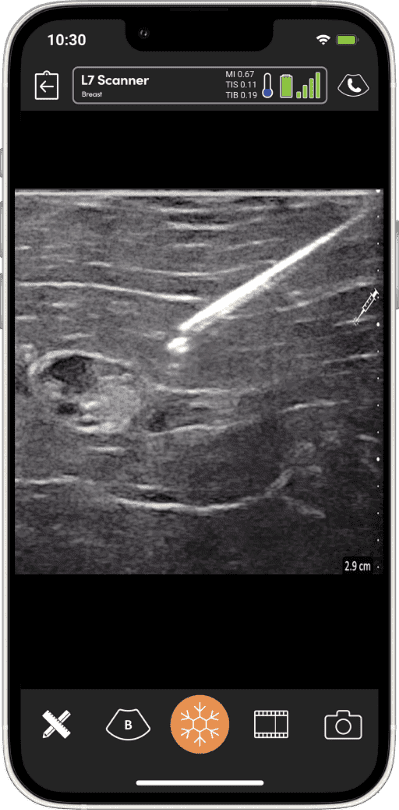

Optimized Imaging for Breast

Using handheld ultrasound allows one to be aware of the exact location of a lesion from the clinic through to the operating room.”

La technologie fournie par l’échographie portable haute résolution Clarius améliore les évaluations au point de service des patientes atteintes de cancer du sein dans mon cabinet de consultation et dans la salle d’opération.